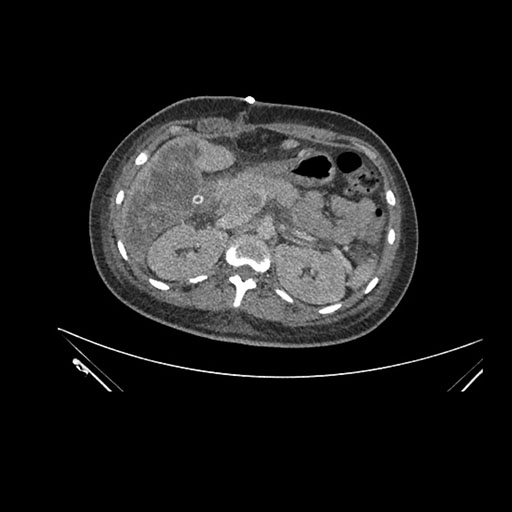

Imaging Analysis

Look through the patient's CT scan to identify any areas of concern for the necessary procedure.

Axial Arterial

Axial Venous

Based on initial findings, which issue(s) would you be most concerned about?